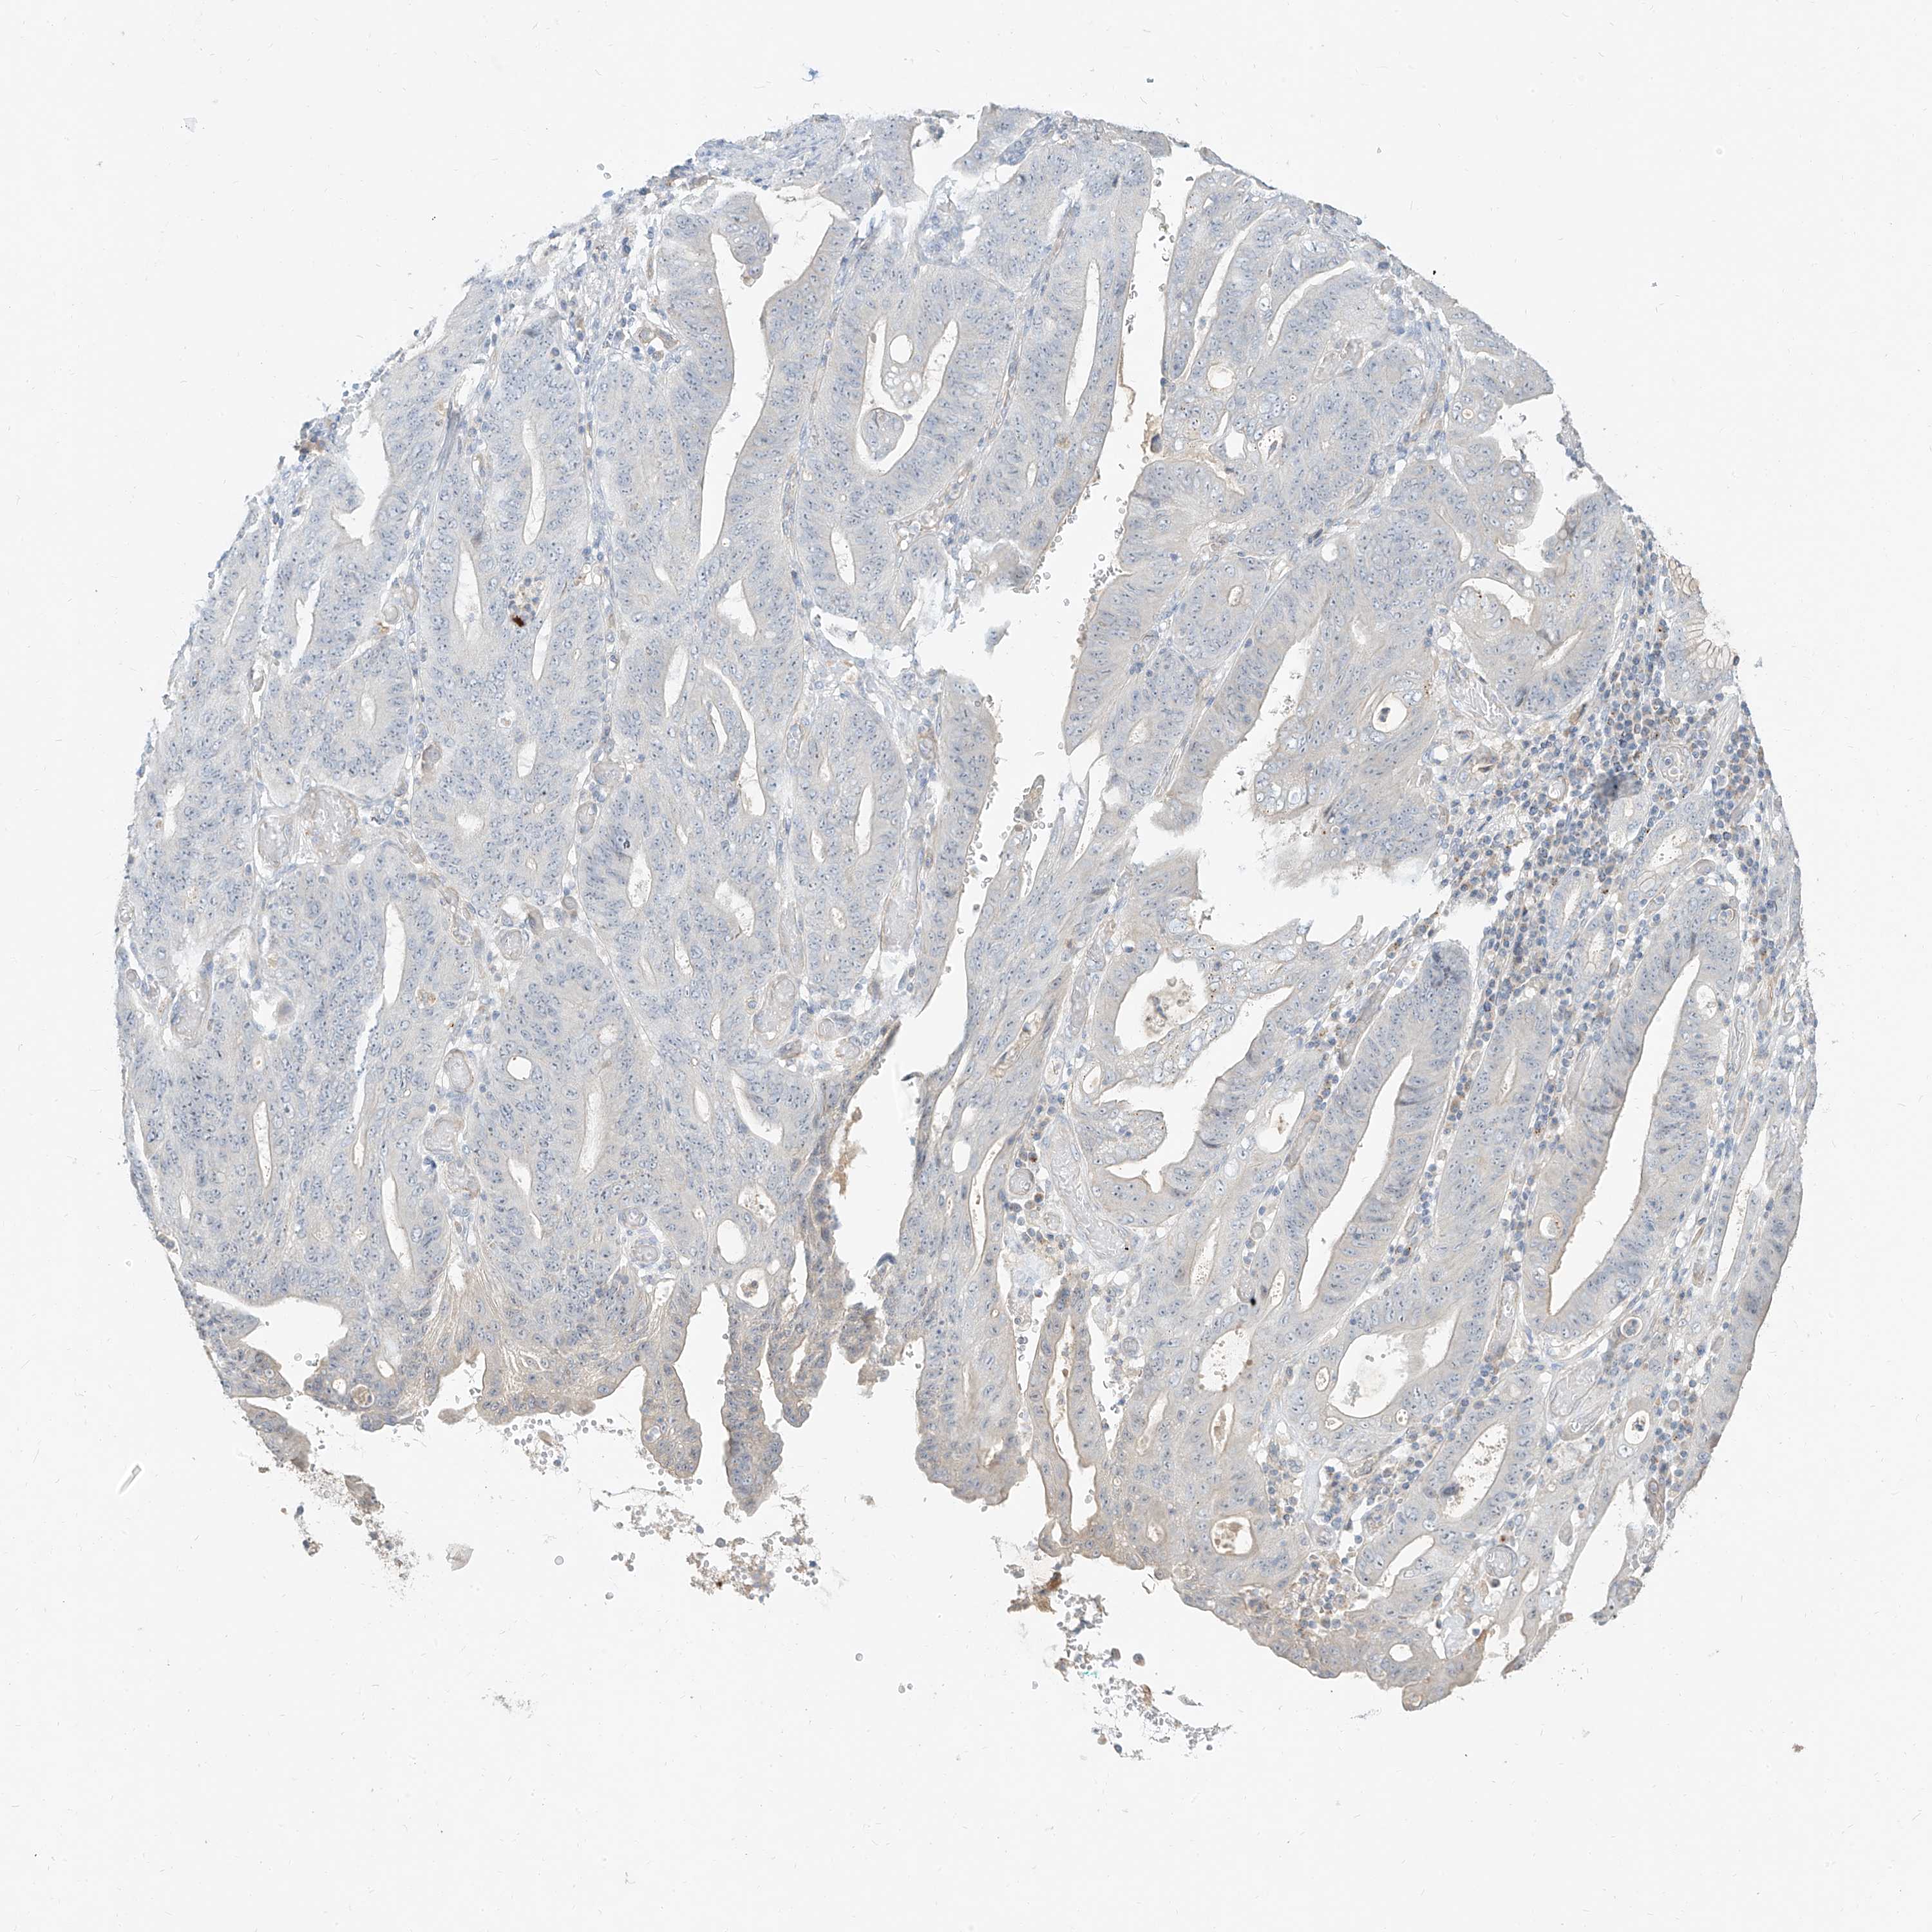

STOMACH CANCER - Protein expressioni

A mouse-over function shows sample information and annotation data. Click on an image to view it in a full screen mode. Samples can be filtered based on level of antibody staining by selecting one or several of the following categories: high, medium, low and not detected. The assay and annotation is described here.

Note that samples used for immunohistochemistry by the Human Protein Atlas do not correspond to samples in the TCGA dataset.

Antibody stainingi

Antibody staining in the annotated cell types in the current human tissue is reported as not detected, low, medium, or high, based on conventional immunohistochemistry profiling in selected tissues. This score is based on the combination of the staining intensity and fraction of stained cells.

Each image is clickable and will lead to virtual microscopy that enables deeper exploration of all samples and also displays staining intensity scores, fraction scores and subcellular localization as well as patient and tissue information for each sample.

Adenocarcinoma, NOS